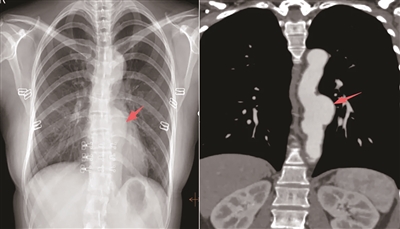

王女士在进行入职体检时,我们敏锐地发现其胸片检查显示纵隔影增宽,胸主动脉区域存在可疑膨隆,于是建议她进一步检查。经CT血管造影(CTA)检查,确诊为胸主动脉瘤——一个随时可能破裂的“高危炸弹”。幸好发现及时,我们在动脉瘤破裂前为王女士进行了微创介入治疗,成功躲避了致命风险。

胸片显示,王女士胸主动脉的形态和大小超出正常范围,这一线索成为诊断的关键点,为治疗争取了宝贵时间。所以,体检中的常规影像学检查绝非“走过场”,而是疾病筛查中至关重要的第一道防线。